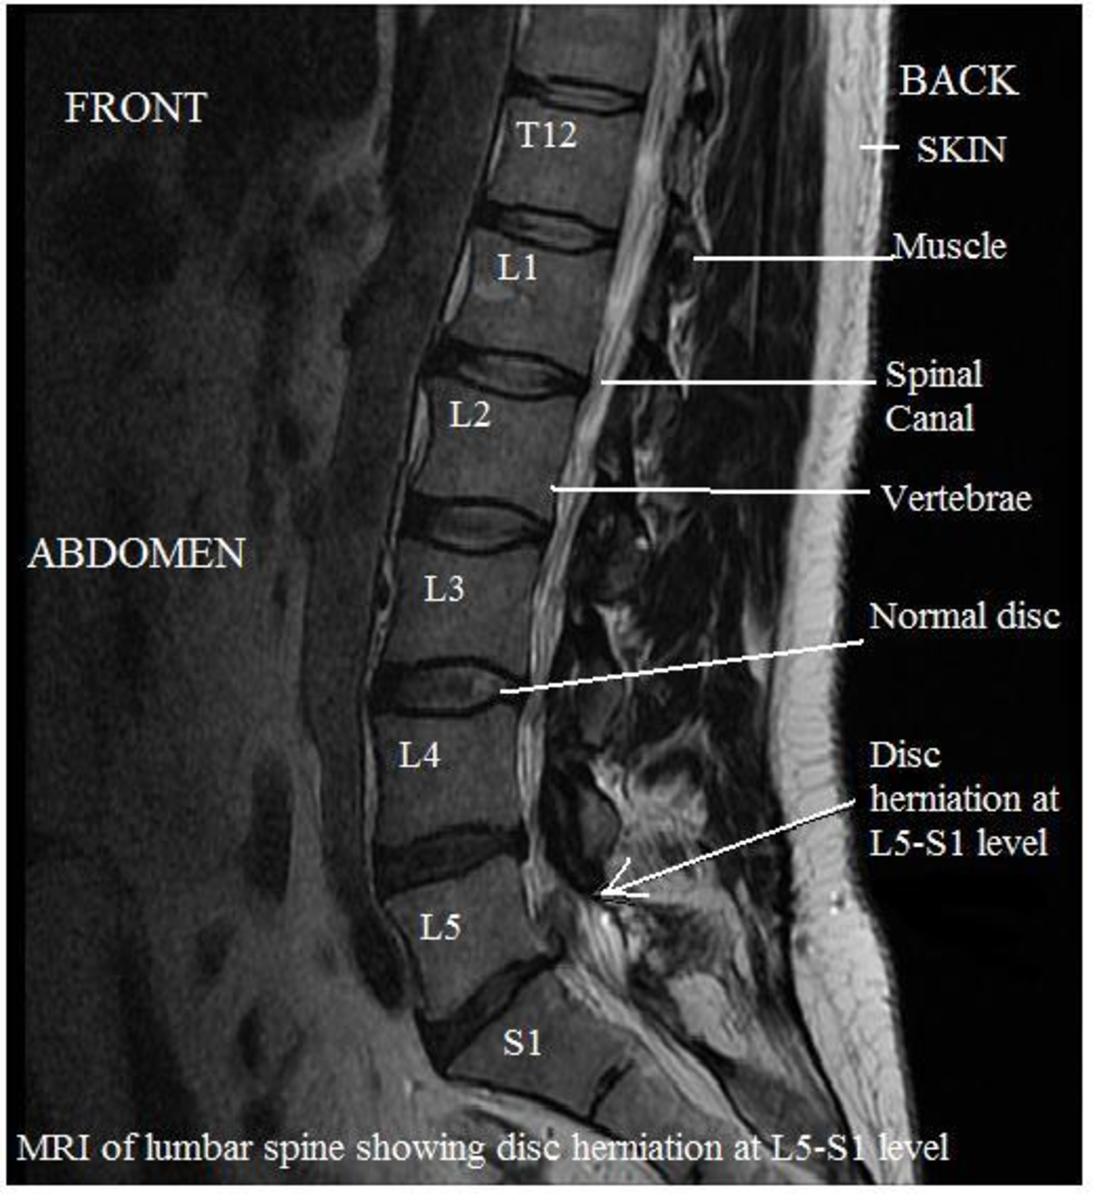

What Is Mri Spine Lumbar And Sacral . Mri of the spine can show spinal alignment, lumbar disk herniation,. Doctors can use mri to examine a person’s lower spine, or lumbar region, and the surrounding tissues. Magnetic resonance imaging (mri) is a diagnostic procedure that uses a combination of a large magnet, radiofrequencies, and a computer to. What is a lumbar spine mri? An mri scan of this area is used to accurately depict soft tissue in and around the lumbosacral spine. The 5 vertebrae of your lumbar spine are numbered from 1 to 5, starting at the top and. Mri scans are considered as one of the main diagnostic tools for the assessment of spinal. The lumbosacral spine consists on average of 5 lumbar vertebrae, the sacrum, and coccyx. To help you prepare, here is a look at the details behind an. Magnetic resonance imaging (mri) uses radio waves and a powerful magnetic field to create detailed images of the body’s soft tissues, organs, muscles and. If your doctor has recommended an mri of your lumbar spine, you might be wondering what this imaging test shows.